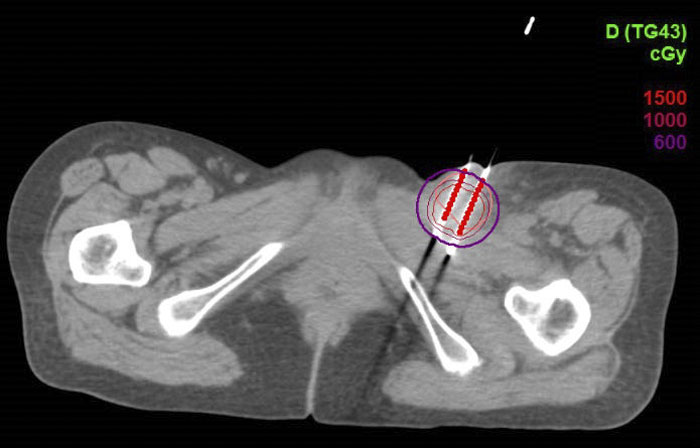

CT引导下的左侧腹股沟淋巴结组织间插植剂量图

该患者的淋巴结转移病灶在浅表,外照射剂量无法达到根治效果,且易出现皮肤破溃等放射损伤。选择CT引导下无痛组织间插植近距离放疗,可实时调整金属针的进入方向和位置,针对肿瘤给予更适形、更精准的放射治疗,在根治肿瘤的同时有效减少了周围正常组织的放射损伤。

CT影像引导下的三维插植近距离放疗,可通过三维视角来进行施源器的植入与固定,定位更精确,该治疗已广泛应用于宫颈癌、子宫内膜癌等妇科恶性肿瘤患者。根据靶区的不同,可以个体化植入施源器,更准确地定位肿瘤组织的位置,通过非共面多角度进针,使肿瘤放疗靶体积达到处方剂量要求,在给予高剂量照射的同时,保证肿瘤周围正常组织受到照射的剂量控制在可接受范围内,从而提高患者的治疗效果和安全性,为晚期难治性妇科恶性肿瘤患者提供了新的治疗希望。